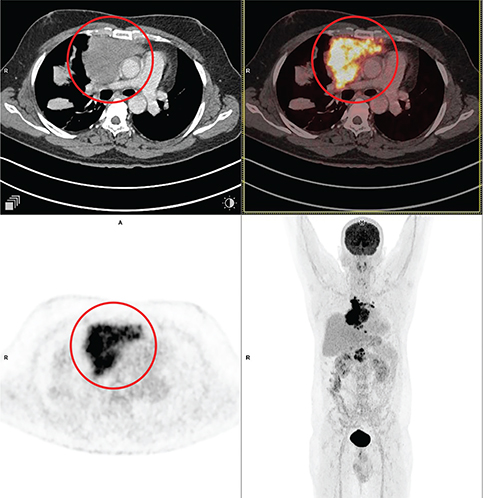

Mediastinal seminomas account for ~ 70% of extragonadal germ cell tumors in the adult population (38). On CT, mediastinal seminomas usually appear as large, homogeneous lobular masses with mild contrast enhancement. Sometimes they might have cystic, hemorrhagic, or necrotic components as seen in Figure 3. Residual mediastinal mass may persist after chemotherapy, and 18F-FDG PET/CT has been used to detect untreated viable disease. In masses greater than 3 cm, Becherer et al. (39) noticed that PET predicted residual viable tumor with a sensitivity of 80% and a specificity of 100%, compared to 73% for CT. Although specificity was much lower at 47% in another multicenter trial, sensitivity was still very high (40).

Fig 3

Figure 3. Seminoma. Anterior mediastinal mass that was pathologically confirmed as seminoma. FDG PET/CT images include axial CT (top left panel), fused axial PET/CT (top right panel), axial PET (bottom left panel), and maximum intensity projection (MIP) PET image (bottom right panel). In the red circle, a well-defined heterogeneously FDG avid and mildly enhancing lobulated soft tissue mass is seen in the anterior mediastinum on left side of midline. Non FDG avid non enhancing hypodense area seen within the mass representing necrotic component. The mass encases the arch of aorta.